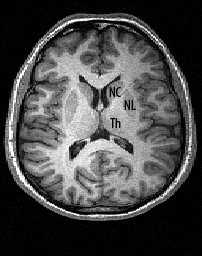

При центрально (аксиально) расположенных объёмных образованиях могут вовлекаться желудочки мозга и расположенные вокруг них подкорковые (базальные) ядра . Зрительный бугор (thalamus), подбугорье (hypothalamus), подбугорная область (subthalamus) и надбугорье (epithalamus) относятся к промежуточному мозгу (diencephalon), составной части ствола мозга.

МРТ головного мозга. Аксиальный срез. Боковые желудочки и подкорковые ядра (NC- хвостатое ядро, NL - чечевицеобразное ядро, Th - зрительный бугор). Инфратенториально расположены части ствола мозга (нижняя часть среднего мозга, мост и продолговатый мозг) и мозжечок.